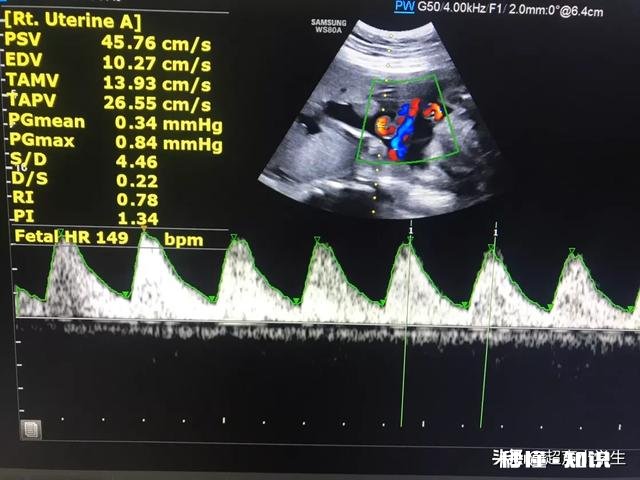

生男生女总是能触动到宝妈们的心,关于生男生女的传闻也是五花八门,今天我们来谈谈胎心率判断男女的真伪,用辩证的方式了解是否可靠 。

很多科普只是讲男宝的胎心率往往会比女宝的胎心率慢,但是具体慢多少呢,或者是哪个数值呢,好像没有断论 。有种说法是,胎儿心率低于140次/ 分,是男孩;高于140次/ 分,则是女孩 。

这种说法准吗?回答是肯定的不准,胎心率怎么可能跟性别有关联呢 , 在正常情况下,胎心率在110-160次/分 , 并随着孕周的增加胎心率会慢慢下降 , 这主要的原因是胎儿的不断发育导致控制胎心率的迷走神经功能逐渐完善导致的 。

至于胎心率小于140次/分是男宝的依据主要来源于成人素材,在成人的世界中男性往往心率较女性慢,但是不是每一个男性的心率都比女性慢呀,所以断论男宝的胎心较女宝的胎心慢不可靠,而且胎心率是时刻在变化的 , 并且会根据宝宝是否运动,是否发热,是否感染,是否服用特殊药物 , 都会引起胎心率变化 , 你也不能因为胎心率一会儿大于140次/分,一会小于140次/分 , 告诉我宝宝即是男的也是女的吧 。